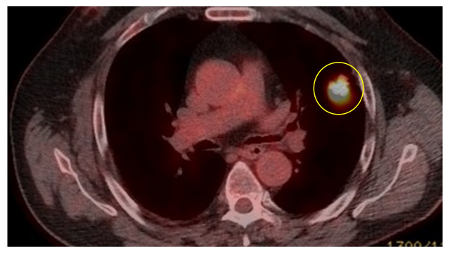

The Herder model (that incorporates F-18 fluorodeoxyglucose [FDG] avidity) has been found to be more accurate in patients who undergo positron emission tomography (PET-CT) evaluation of pulmonary nodule.[38][39] UK guidelines recommend that selected patients (pre-test probability of malignancy >10% and solid component of a nodule greater than the local threshold size [usually 8 to 10 mm]) are evaluated by PET-CT and that the Herder model is used to determine risk thereafter.[4][40]

[Figure caption and citation for the preceding image starts]: PET CT scan with 18-fluorodeoxyglucose (18-FDG) showing a high uptake peripheral left lung lesion. Surgical resection confirmed a moderately differentiated squamous cell lung cancerFrom the collection of Dr George Tsaknis, MD, PhD, FRCP(London), MRQA, MAcadMEd, PGCert; used with permission [Citation ends].